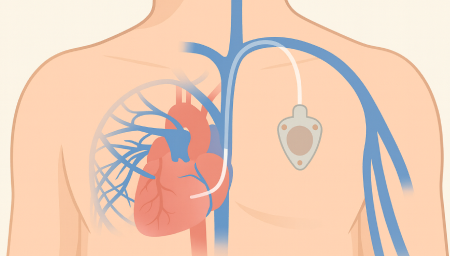

항암관(Chemoport)삽입

Chemoport는 항암제처럼 자극이 강한 약물을 안전하고 안정적으로 투여하기 위해 흉부 피부 아래에 이식하는 중심정맥 사용 포트입니다. 팔 혈관이 약하거나 반복 주사로 인한 통증이 걱정되는 환자에게 도움을 줄 수 있으며, 장기간 치료가 필요한 경우 편안하게 항암 치료를 지속할 수 있도록 설계되어 있습니다.

Chemoport는 피부 아래에 완전히 이식되는 구조라 반복적인 바늘 찌름을 줄일 수 있고, 장기간 안정적인 항암제 투여가 가능합니다.또한 샤워 시에도 물이 닿지 않아도 되고, 외관 노출이 적어 일상생활에서 불편감이 비교적 적습니다.